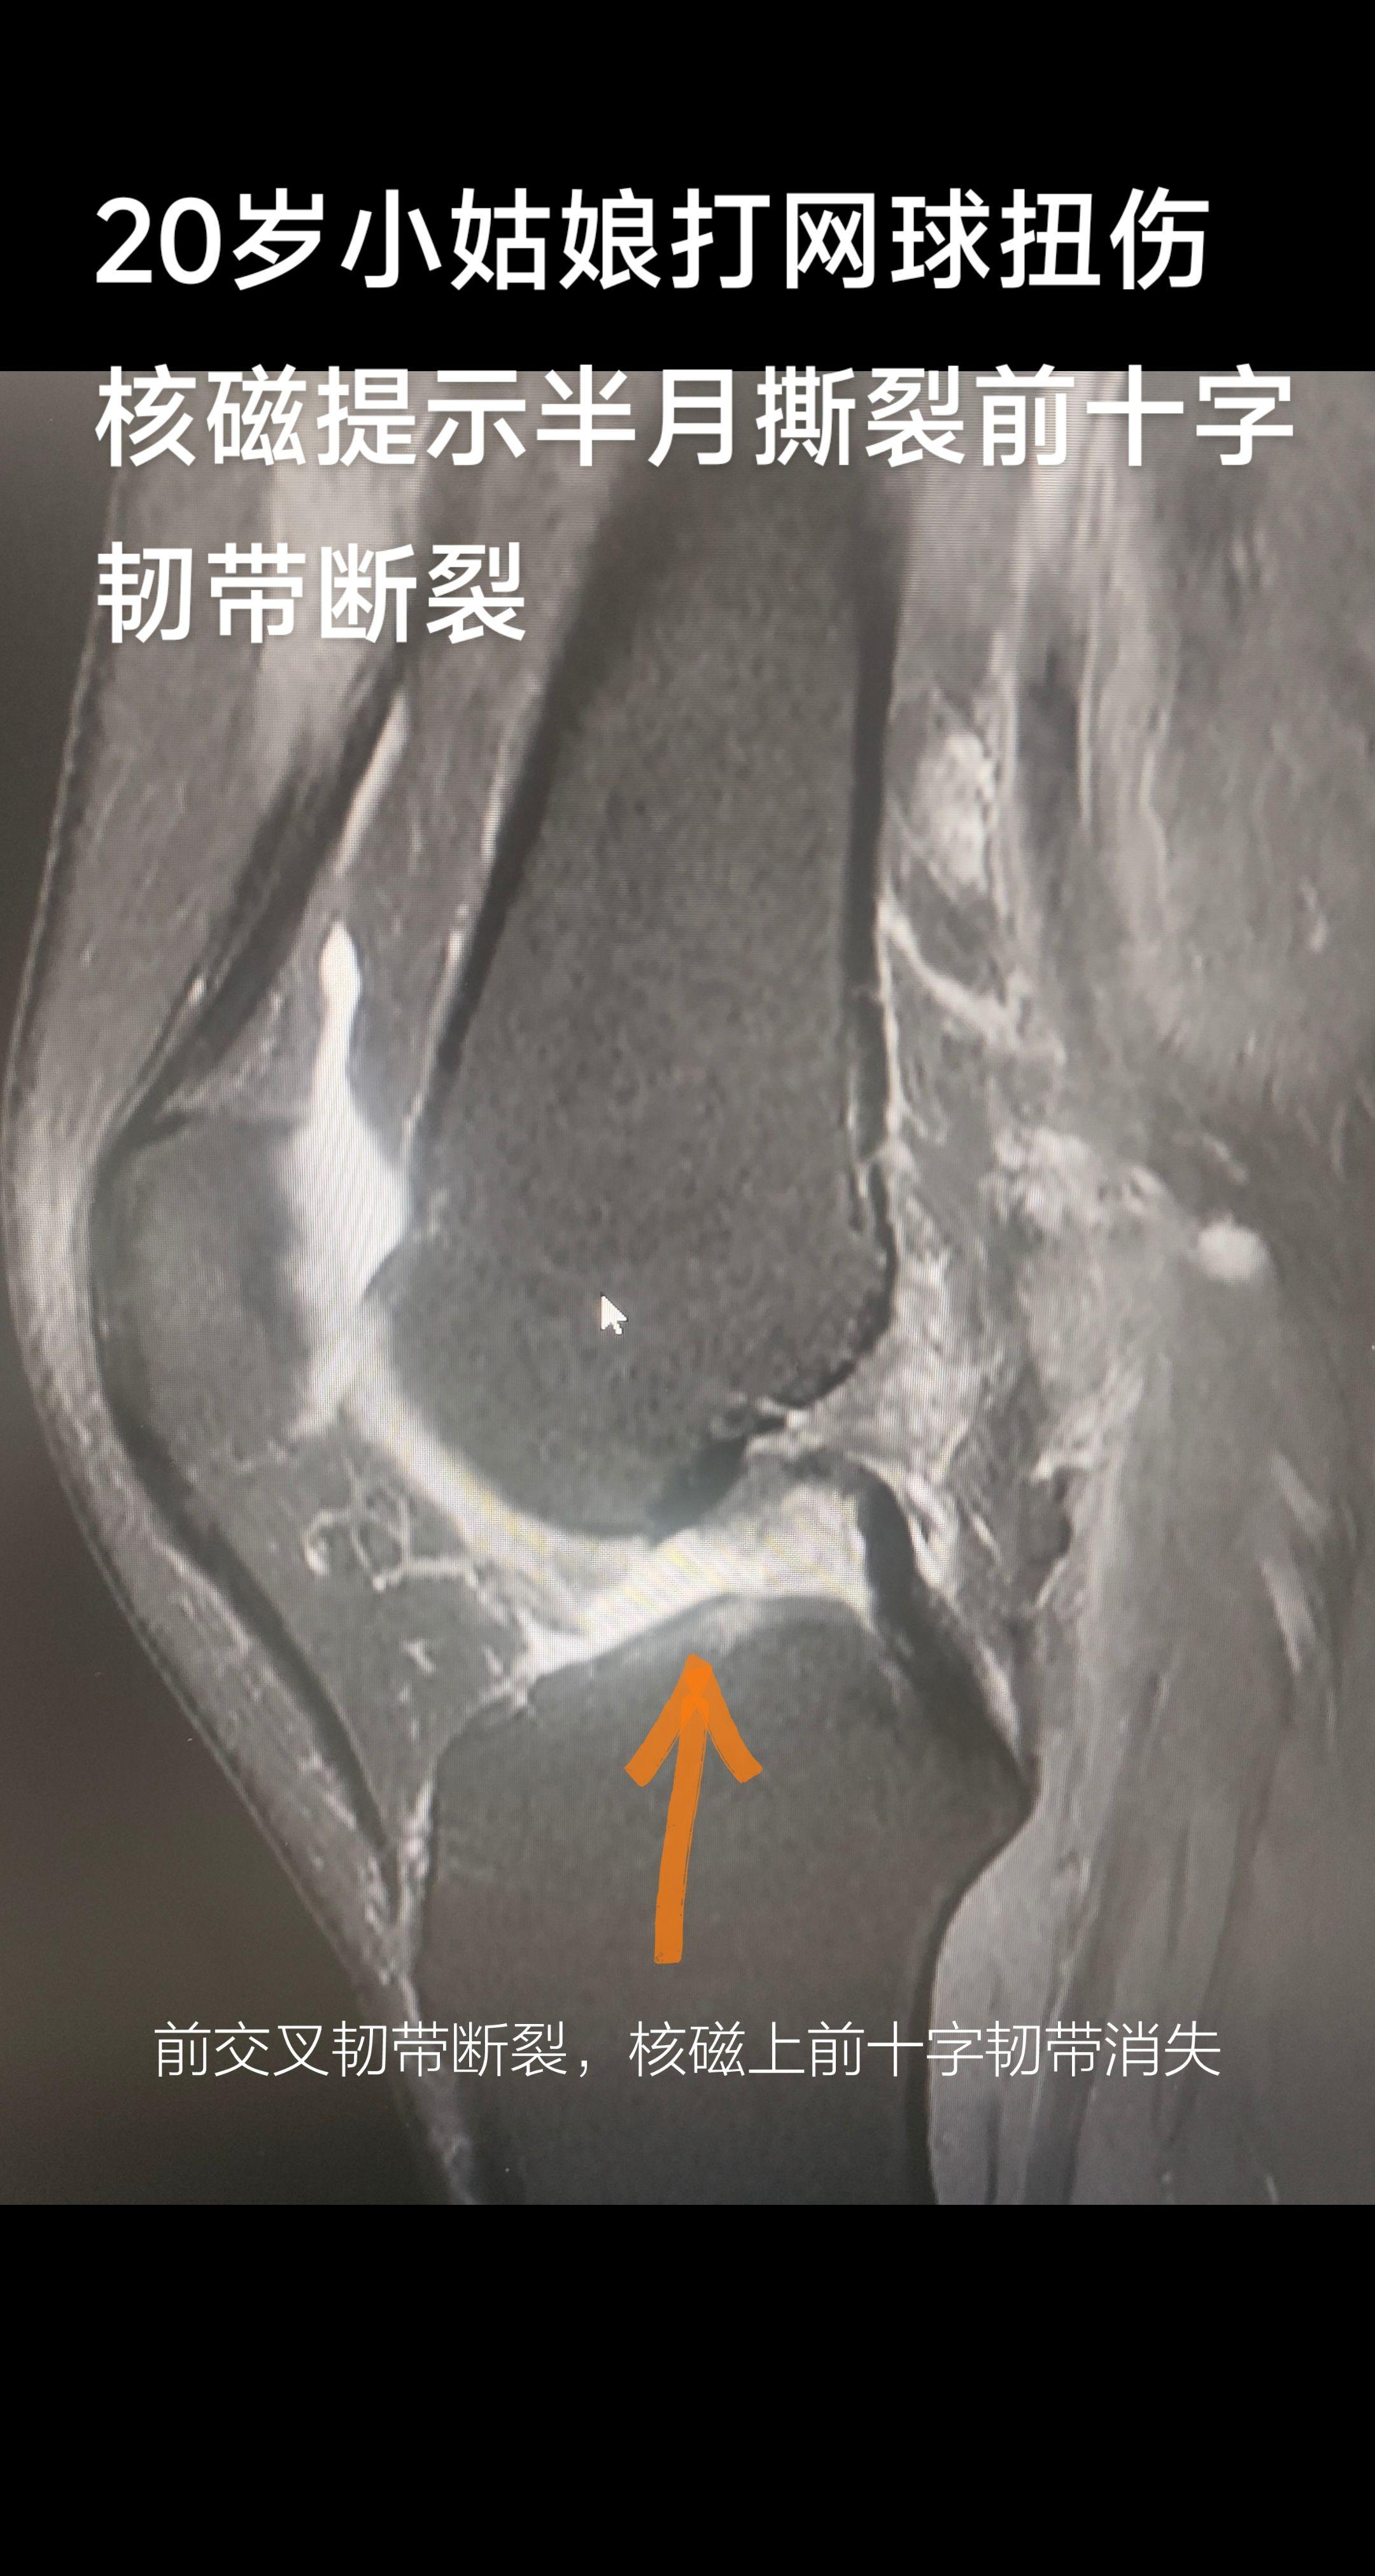

膝关节十字韧带断裂。